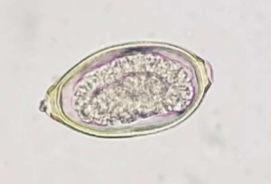

Pearsonema plica/ Pearsonema feliscati

bladder worm of dogs, foxes, and cats

what lifecycle does Pearsonema plica/ Pearsonema feliscati have

indirect; earthworm is the intermediate host

symptoms of Pearsonema plica/ Pearsonema feliscati

usually asymptomatic, but can cause blood in urine, irritated bladder